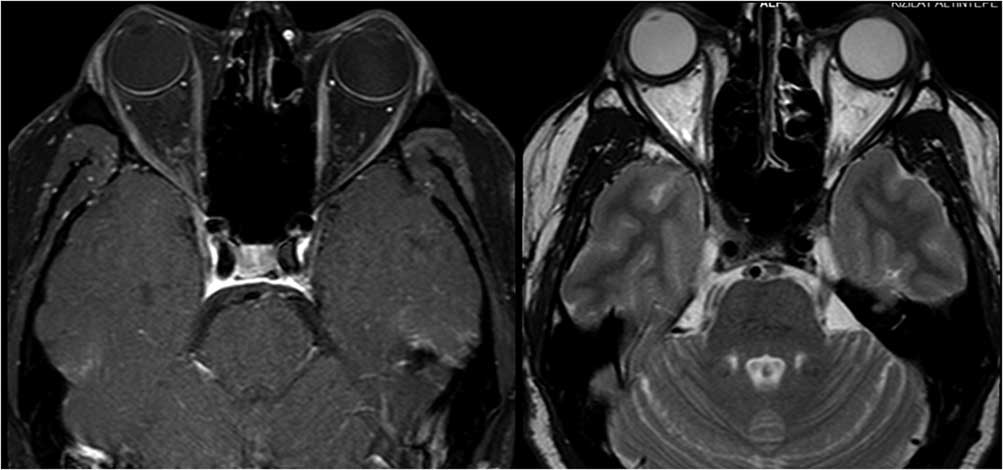

Case 3: A 74-year-old male was admitted with a 1.5-year history of blurred vision and progressive bulging of both eyes. The symptoms started after nasolacrimal duct intubation surgery to treat lacrimal drainage obstruction. He had a past medical history of vision loss in his left eye due to trauma 10 years previous, as well as erosion and perforation of the nasal septum 2 years before. Neurological examination showed bilateral proptosis that was more prominent on his right eye, and his extraocular movements were limited bilaterally in all directions (Figure 3a). MRI of the orbit identified bilateral hyperintensities, enlargement, and contrast enhancement in extraocular muscles. Brain MRI findings included linear dural thickening and enhancement on the anterior frontal and temporal lobes, inflammation and enhancement on the maxillary, frontal, and sphenoid sinuses, and a nasal septum defect (Figure 3b). Investigations revealed a mild increase in CRP and sedimentation rate, slightly low T3 and T4 levels, and normal thyroid-stimulating hormone, CBC, antithyroid antibodies, viral serology, IgG4 levels, ANA, and anti-AChR antibodies. The anti-proteinase ANCA (anti-PR3 ANCA) level was 72.3 U/ml (>20 U/ml), and p-ANCA was found to be positive. Therefore, a diagnosis of orbital inflammation due to GPA was established. Chest CT revealed calcific lung nodules and bilateral apical pleuroparenchymal fibrotic density changes. Histopathological investigation of nasal biopsy revealed chronic inflammation. He was treated with high-dose IV methylprednisolone (1 mg/day for 5 days) followed by 60 mg/day oral prednisolone. He responded with a prompt reduction of proptosis and lid edema and a slight improvement in ocular movement over the 6-month period. Treatment continued with prednisolone tapering and azathioprine.

Figure 3b Axial and coronal MRI showing bilateral hyperintensities, enlargement, and contrast enhancement in extraocular muscles, linear dural thickening, and enhancement on the anterior frontal and temporal lobes, enhancement on the maxillary, frontal, and sphenoid sinuses and nasal septum defect. Right bulbus oculi was normal, whereas left bulbus oculi revealed retinal detachment.